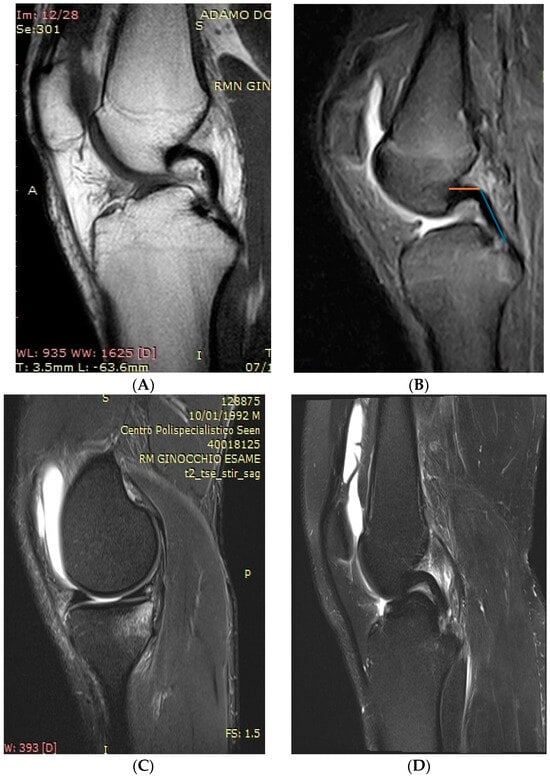

Rotatory instability was evaluated with the pivot shift test. It was graded according to the classification by Jacob et al. [14], with Grade 1 being abnormal movement when the leg was held in a neutral position and Grade 3 being when abnormal movement was observed when the leg was held in external rotation. The integrity of the MCL and LCL was confirmed with the varus and valgus stress test. MRI as well as X-rays (including weight-bearing lateral view with the knee at 15° flexion) of the involved knee were available for all patients and were performed within 20 days prior to surgery. All imaging measurements were carried out on digital X-ray using a DICOM medical image viewer (Horos Project; Purview, Annapolis, MD, USA). On the lateral view of the X-ray, the posterior tibial slope was measured according to the method described by Dejour et al. [15]. The proximal anatomic axis of the tibia was first drawn by connecting the midcortical diameters of the tibia 5 and 10 cm distal to the joint line. A reference line was created perpendicular to this anatomic axis. Tibial slope was defined as the angle between the reference line, and a line was drawn tangent to the uppermost anterior and posterior edges of the medial tibial plateau (Figure 1).

Figure 1. The posterior tibial slope was measured according to the method described by Dejour et al. [15] using the true sagittal view to measure the angle between the line perpendicular to the tibial diaphyseal axis (violet line) and the tangent to the most superior points at the anterior and posterior edges of the medial tibial plateau (yellow line).